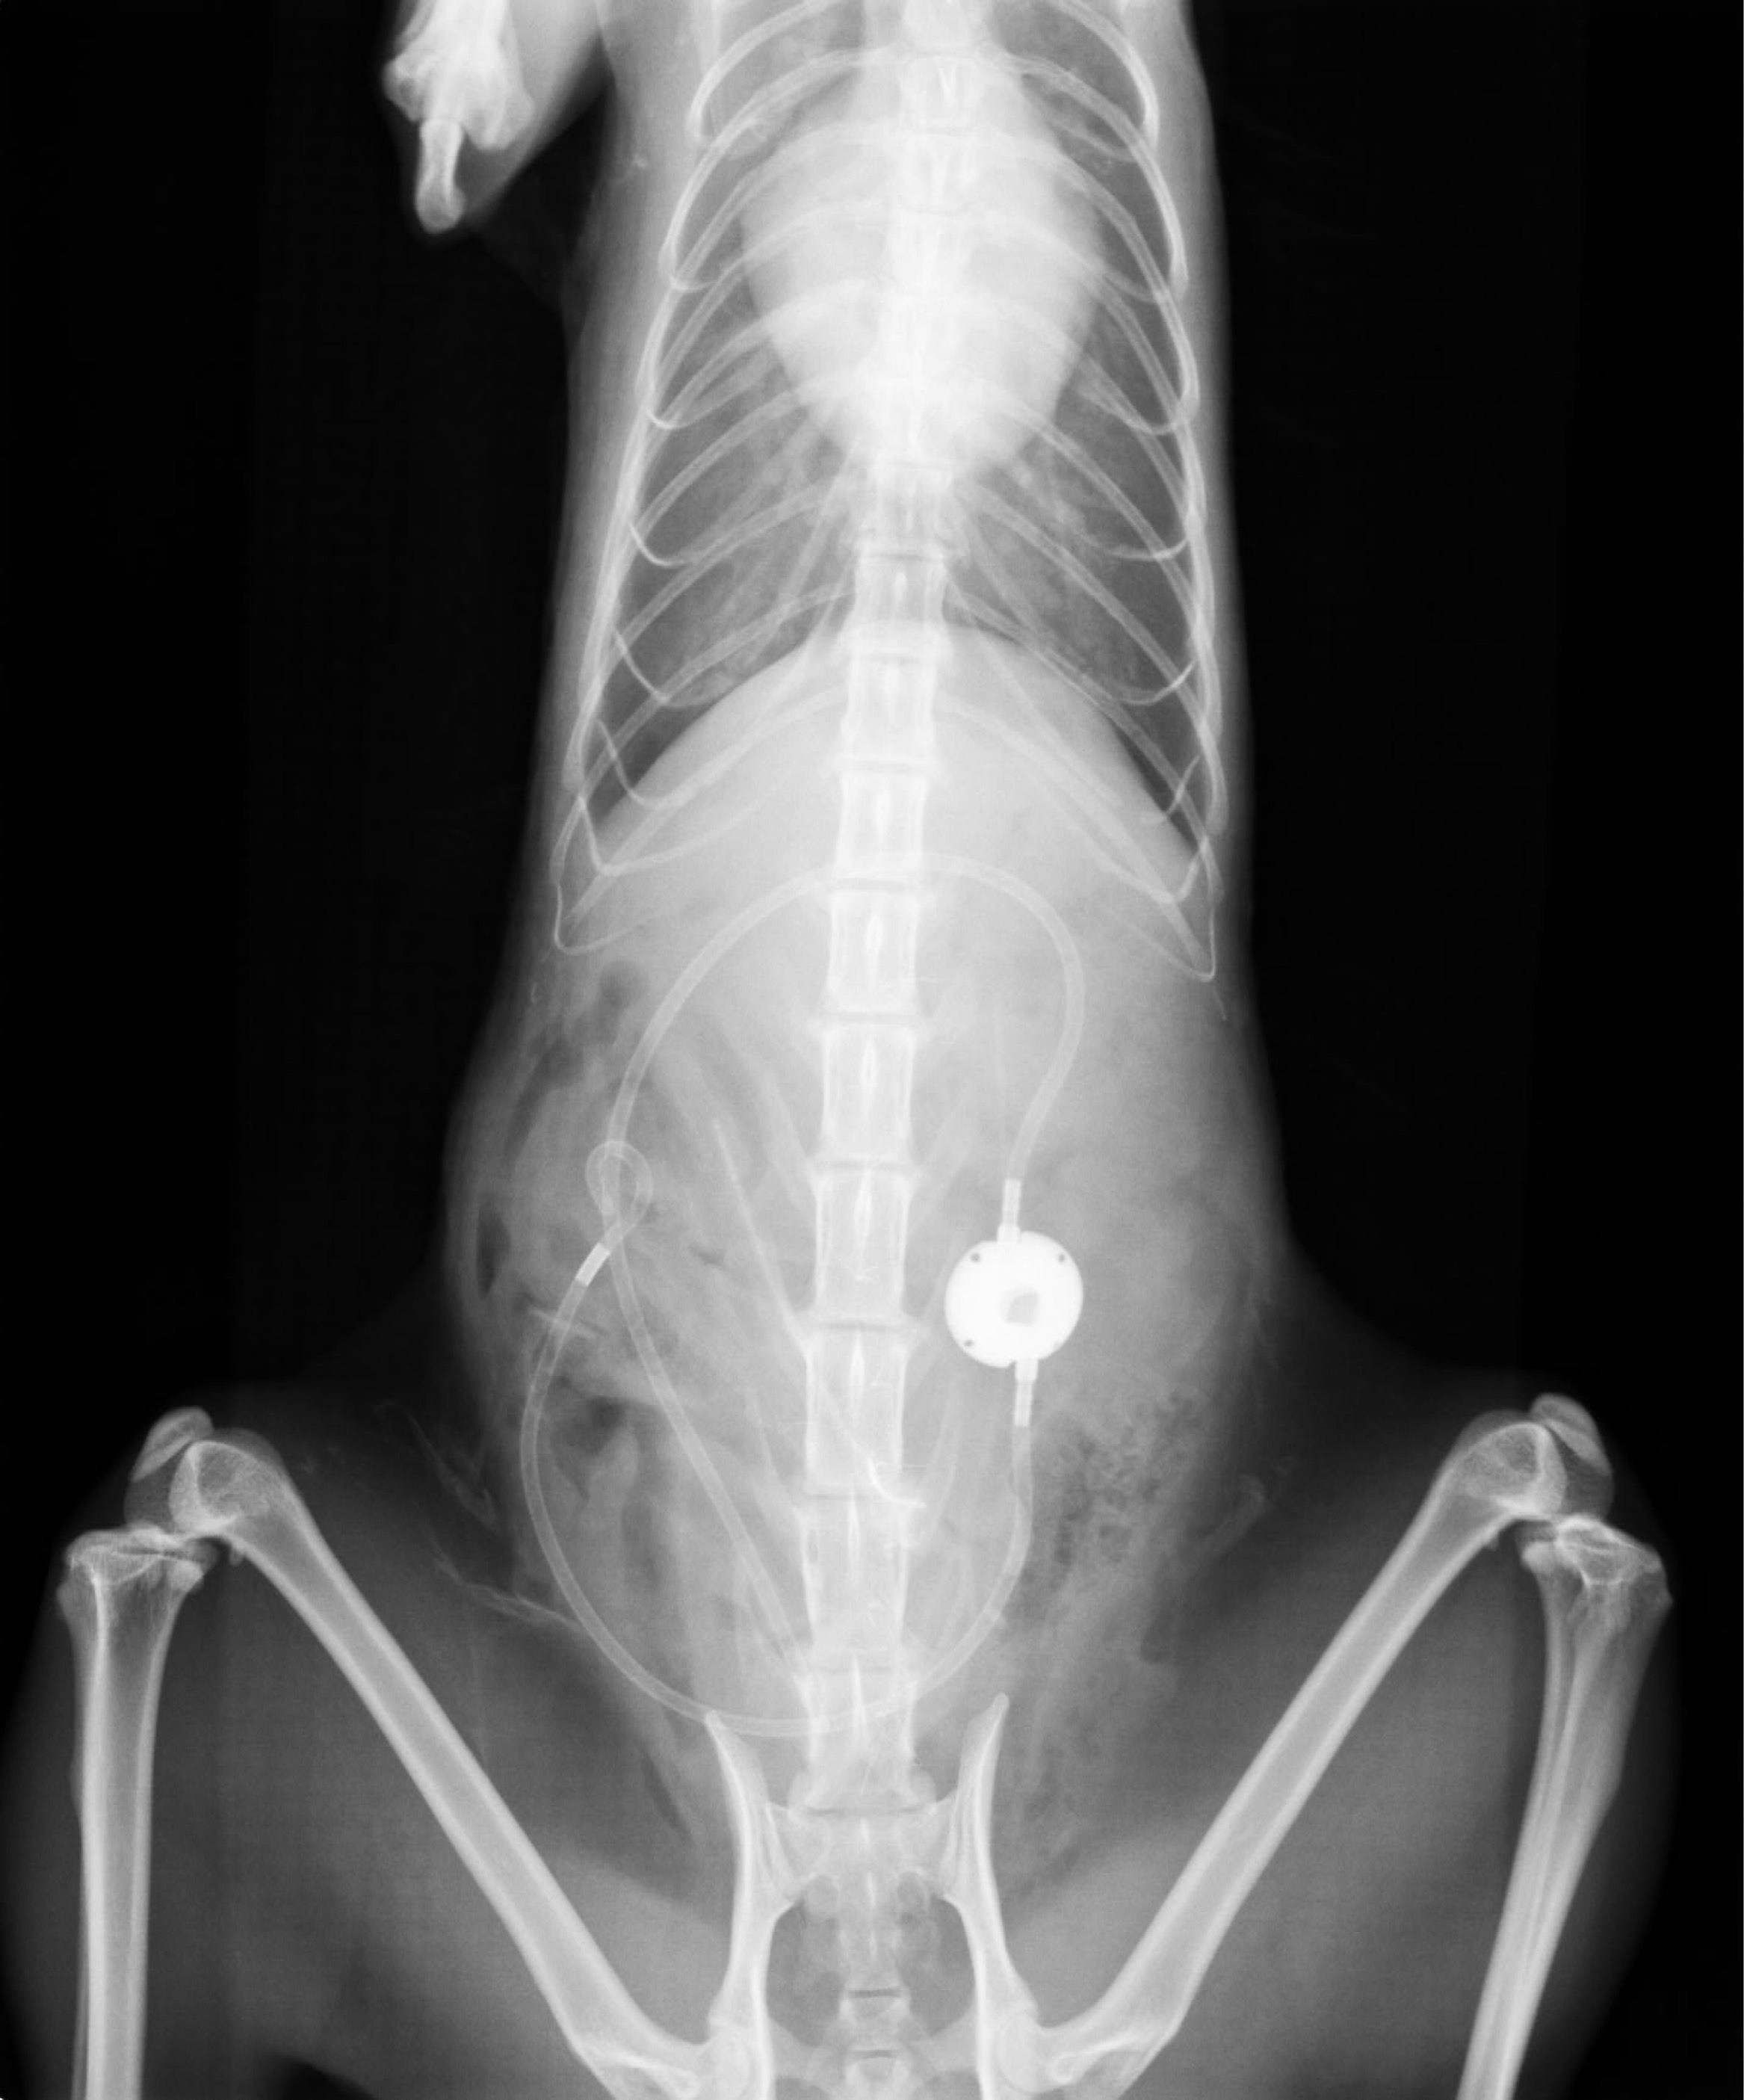

↓術後のなぎのレントゲン写真です。

管のようなものと、丸い影がSUBシステムと呼ばれるものです。